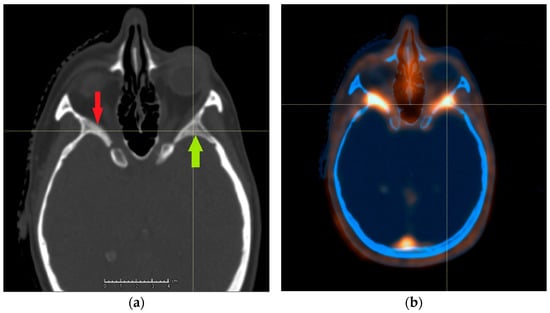

A crucial step in the application of such a highly conformal radiation technique is the proper definition of tumor extent. The standard aid to native planning CT is the contrast-enhanced MRI, which has the ability to differentiate between soft tissues including meninges superior to the one of CT. In a postoperative situation, its interpretation can be difficult, as scar tissue and normal meninges take up contrast; moreover, rare but known intraosseous and soft tissue extensions could also be either overlooked or overdiagnosed [7,8]. An example of an intraosseous lesion is shown in Figure 1. Meningiomas have been reported to commonly overexpress somatostatin receptor type 2 (SSTR2), and this property can be used to back up structural imaging with a biological study [9]. Multiple groups reported an improvement in tumor extent recognition by using 1,4,7,10-tetraazacyclododecane-1,4,7,10-tetraacetic acid (DOTA)-conjugated PET/CT, yet the available studies featured mixed groups of different meningioma grades and patients treated with different modalities [10,11,12,13]. We, therefore, decided to investigate the impact of DOTA PET/CT on interobserver variability in contouring of meningiomas treated with a uniform protocol and assess the possible clinical consequences.

Figure 1.

Example of an intraosseous extension of meningioma not properly recognized on CT: (a) the right side displays suspicious hyperostosis (red arrow), and the left side appears to have the normal bone structure preserved (green arrow). PET/CT revealed meningioma extension on both sides (b).